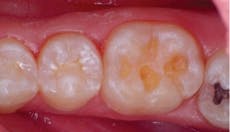

Occlusal composite fill

Additionally, restoring these detected lesions can take on many forms to keep with the minimally invasive theme, including no preparation options such as ICON (DMG/America), to glass ionomers and direct composite resins. Many times, composites offer dentists the most simple and cost-effective way to create esthetic restorations, but not without a significant learning curve. It’s been more than 50 years since Buonocore thought of bonding to enamel with the introduction of acid-etching, and though the resin-based fillings of that period were quite inferior to those available today, issues related to material properties and handling characteristics, as well as the clinician’s skill, are still key to the success or failure of a composite restoration.

Today’s flowable composites allow for more widespread use in both anterior and posterior applications. Some offer larger increment or bulk-fill capabilities due to their low-shrink/low-stress chemistry (SureFil SDR Flow, DENTSPLY/Caulk; GrandioSO Flow, VOCO), while others offer self-adhering properties where a separate dentin-bonding agent is not used (Vertise Flow, Kerr Corp). Not to be outdone, the traditional body composites have been fine tuned to the point where particle size and distribution yield amazingly esthetic results balanced with equally impressive physical properties. These attributes, coupled with innovative and reproducible placement techniques, can elevate the dentist’s ability when using direct composites to create successful, long-lasting restorations.